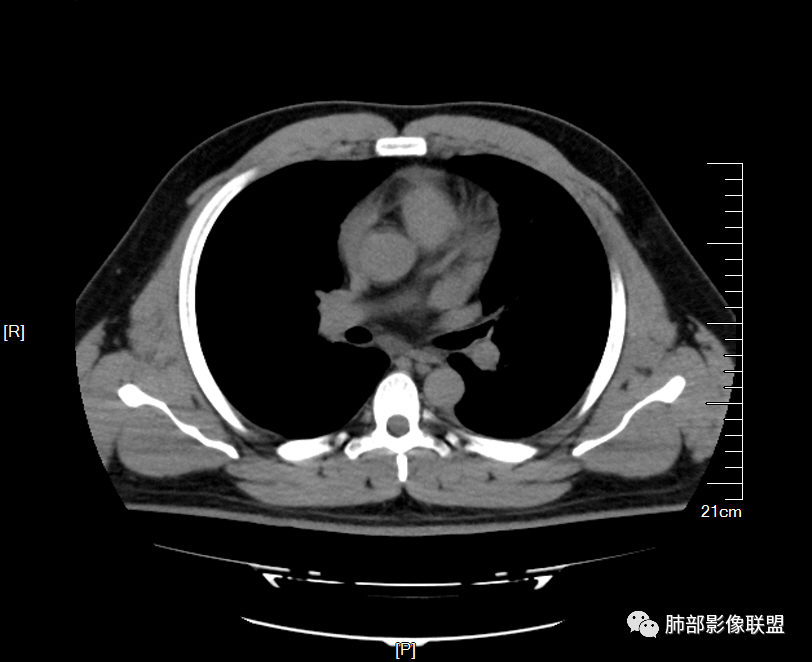

男32岁。既往曾发现血肌酐升高.此次因左足痛6天入院。有痛风、高血压病史。两肺弥漫性的病变,小片状或者结节状为主病变,小叶中心分部为主,边界不清。心影比较饱满,肝实质密度均匀的降低。考虑为肝损害的影像学改变。综合考虑多功能脏器的损害,肺部损害肺泡炎?肺水肿?或病毒性的肺炎?

年轻男性,痛风史,高血压史,肌酐高,左足痛6天入院。胸CT:双肺多发弥漫性磨玻璃结节影,大小不一,部分融合,上中下肺都有,中内带多,胸膜下少。部分血管束略增粗,小叶内间隔、小叶间隔增厚,下肺明显,左室大。叶裂胸膜增厚。临床有痛风,左足痛6天,考虑:心衰、间质性肺水肿?弥漫性肺泡出血?鉴别:MPA,肺肾综合征,痛风结节等。

少量积液,脂肪肝

中轴间质增厚,小叶间隔增厚,小叶内间质增厚,部分重力作用,双侧对称,胸水,按理淋巴道回流受阻有

肺水肿肯定有

但是单纯性肺水肿不好解释